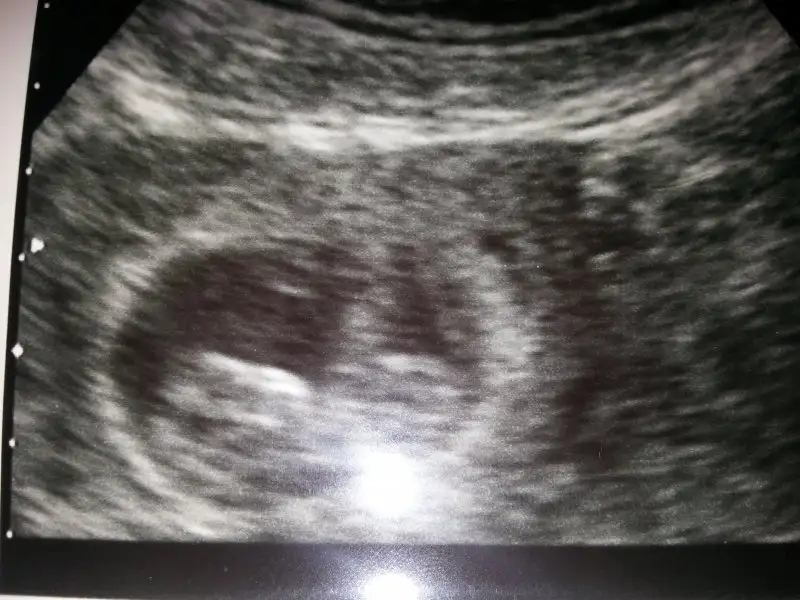

Merhaba kızlar nasılsınız biz pazartesi günü Kasık ağrısından hastaneye gittik 6+5 di kesemiz göründü fakat Dr bebek yok dedi siz kaç haftalikken gördünüz bebeklerinizi salı günü tekrar gidicez hakkımızda hayırlısı olsun